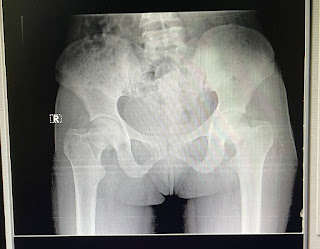

SHORT CASE 1 :

A 40 year old female patient came with complaints of pain in the both hips since 6months

History of present illness :- Patient was apparently alright 6months back,then she developed pain in the both hip regions which is insiduous onset,gradually progressive,aggrevated on walking,getting up from sitting posture,relived on taking medications.

Trandelenberg Test : Positive on both sides

PROVISIONAL DIAGNOSIS:

The above features suggestive of connective tissue disorder - sjogrens syndrome ( Dry eye, Dry mouth ,biopsy of labium is positive for sjogrens )

Right hip pain secondary to ? Bone involvement spondyloarthropathy

Hypokalemic periodic paralysis secondary to distal Renal tubular acidosis

X ray pelvis